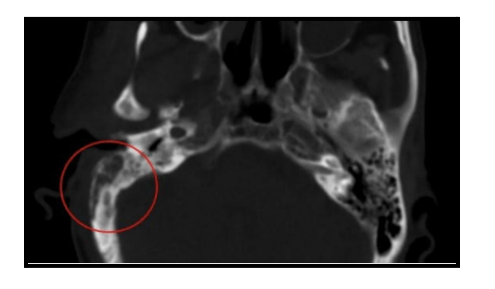

The diagnosis is primarily clinical, based on symptoms and signs, along with radiological findings from a CT scan. In cases where infection is suspected, a culture of pus (a sample of the discharge) from the ear or a biopsy of the granulation tissue from the external ear canal may be required. Diabetes affect ear by making individuals more susceptible to infections, such as Necrotizing Otitis Externa (NOE), which can complicate the diagnosis.

Necrotizing Otitis Externa (NOE) spreads through the fascial planes, causing erosion of bones and invasion of nearby tissues. This can lead to involvement of cranial nerves and the bones of the skull base. As a result, complications may manifest as facial weakness, hoarseness of voice, difficulty in swallowing, and tongue weakness. In later stages, the infection may spread to the brain parenchyma, leading to severe complications such as brain abscesses and seizures. Diabetes affect ear by increasing the risk of NOE, which can result in these potentially life-threatening complications.